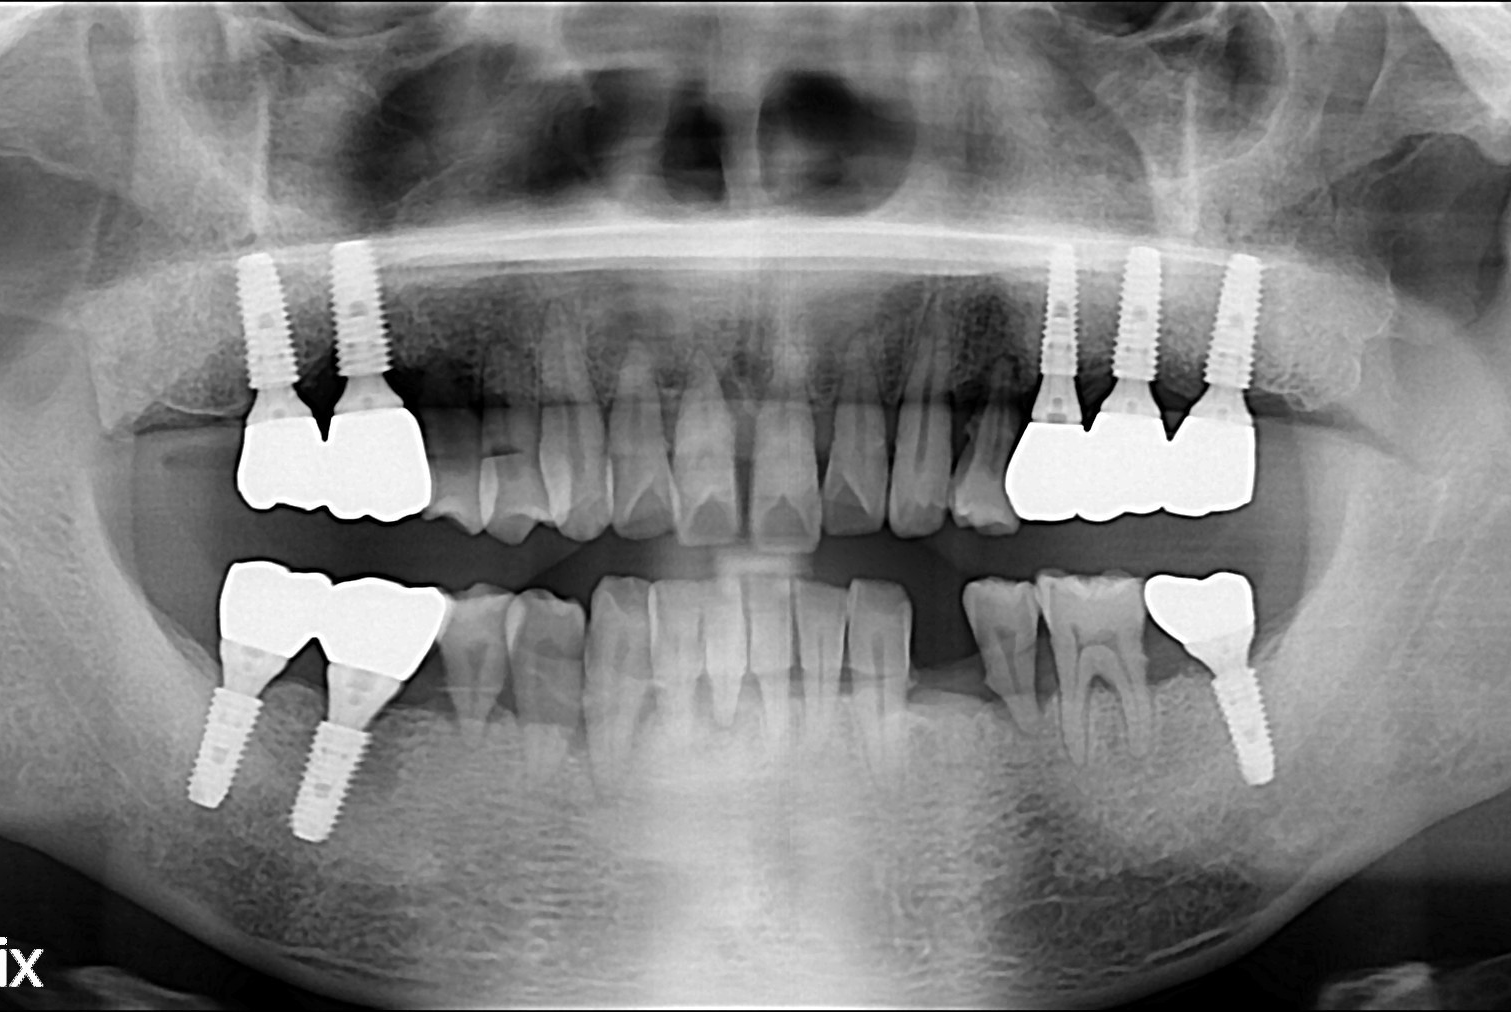

치료후 : 2018-10-19

세종치과는 많은 환자와 다양한 케이스를 바탕으로 항상 편안한 임플란트 수술을 제공하고자 노력하고,

오래동안 튼튼히 쓸 수 있는 임플란트 수술을 가장 큰 목표로 삼고 있습니다